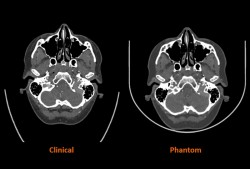

Stratasys oznámil, že uzavřel partnerství se Siemens Healthineers při realizaci přelomového výzkumného projektu, jehož cílem je vyvinout nová moderní řešení pro rozvoj lékařských zobrazovacích fantomů pro zobrazování pomocí počítačové tomografie (CT). CT fantomy, které jsou důležitým nástrojem v lékařském zobrazování a téměř univerzálním zdrojem v nemocnicích ... |